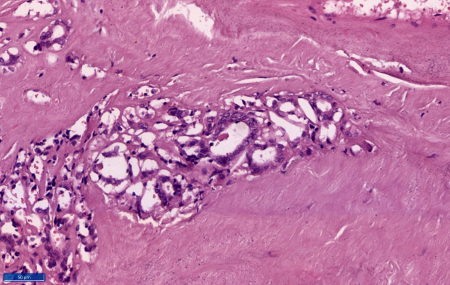

Figure

4: Section shows protrusion of tumour

cells outside the capsule (Haematoxylin

and Eosin, x 100) |